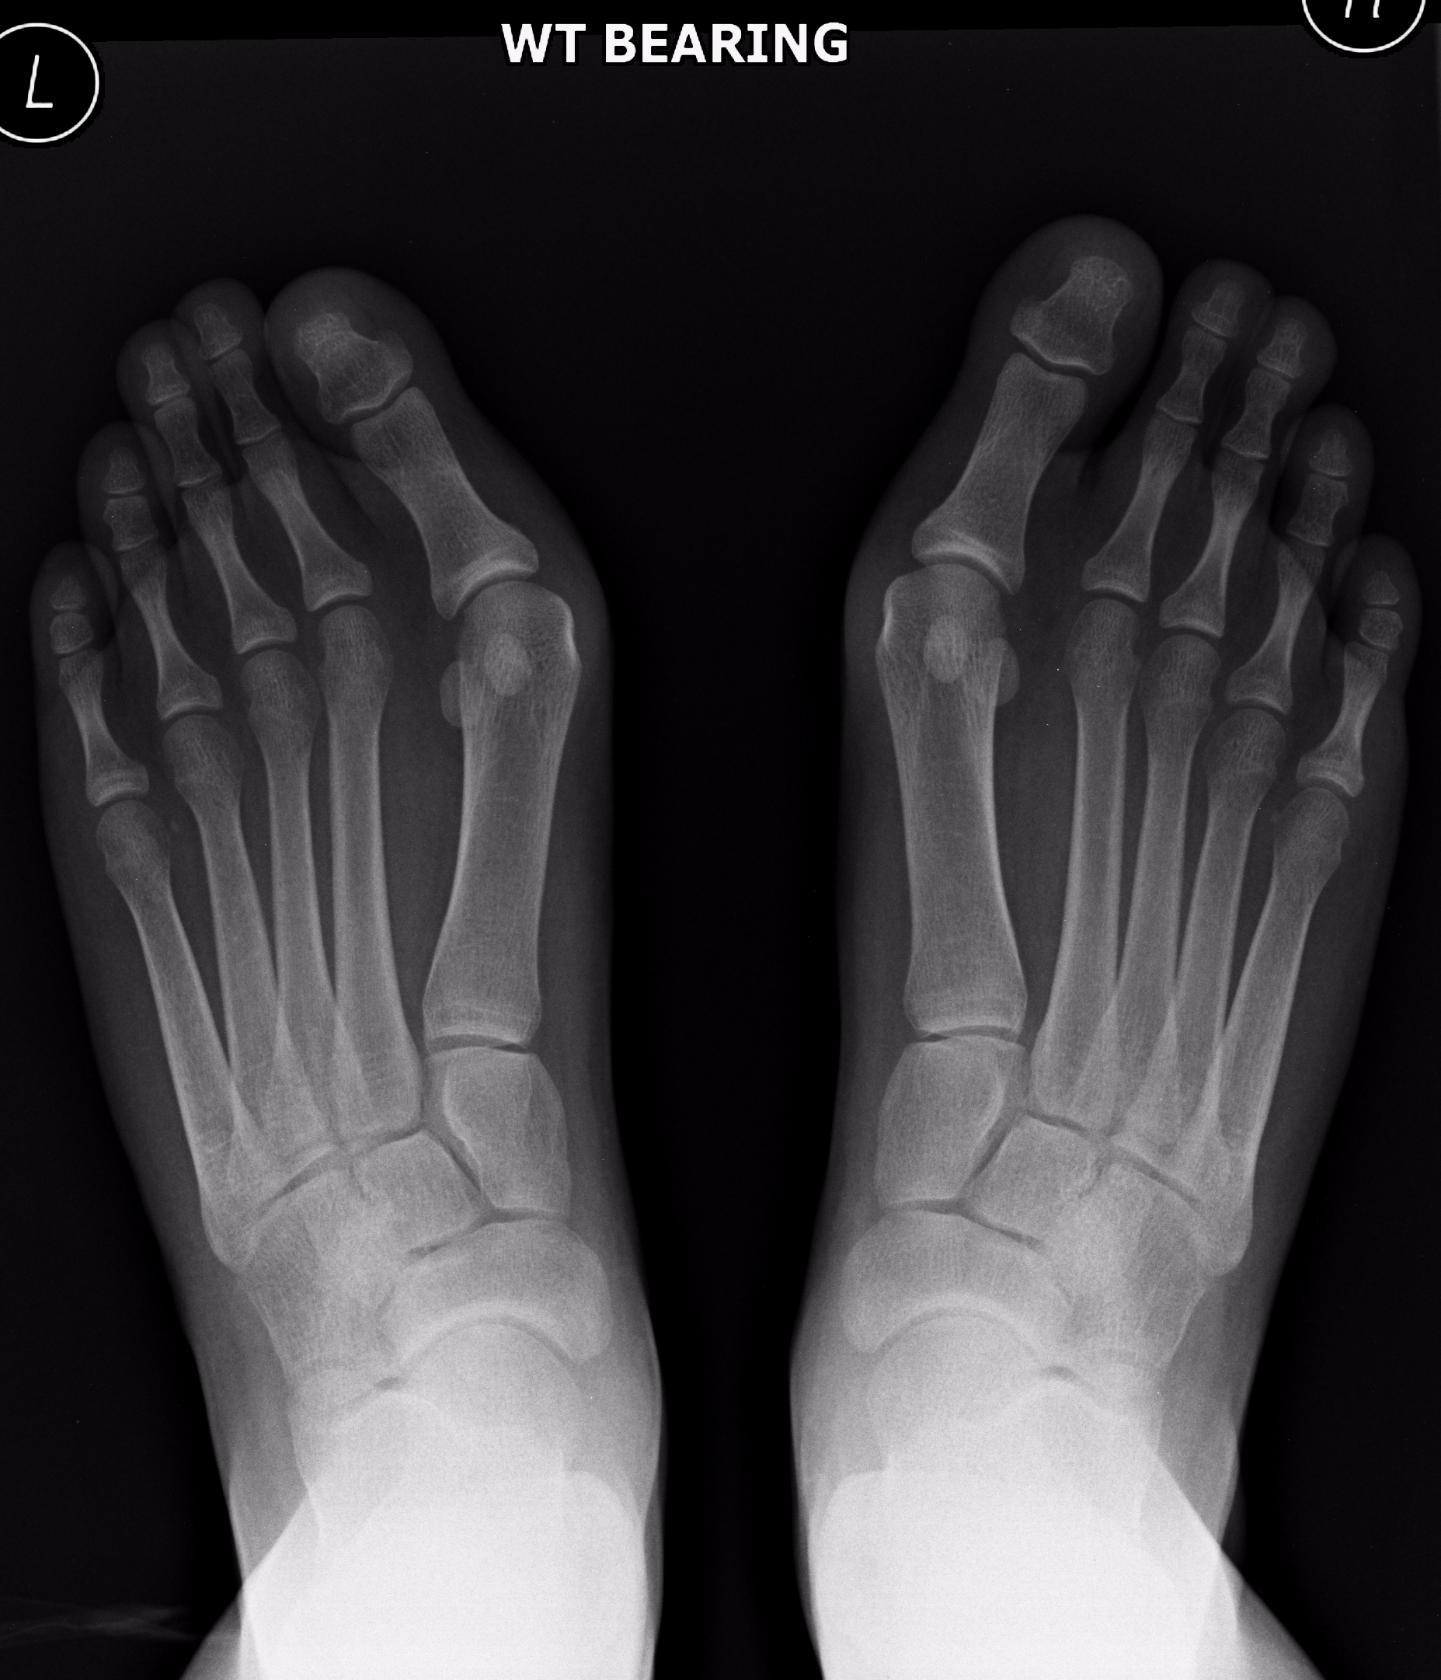

Мало кто знает, что это поперечное плоскостопие, на большом пальце образуется "косточка", этой патологией страдают и дети и взрослые, бывает, как наследственное, если есть у родственников, так и приобретенное, высокий каблук, неправильная обувь. Косточка с возрастом может начать расти буквально в течении полугода, причем запущенный процесс всегда приводит к заболеваниям суставов и позвоночника, так же страдают вены(Варикоз).